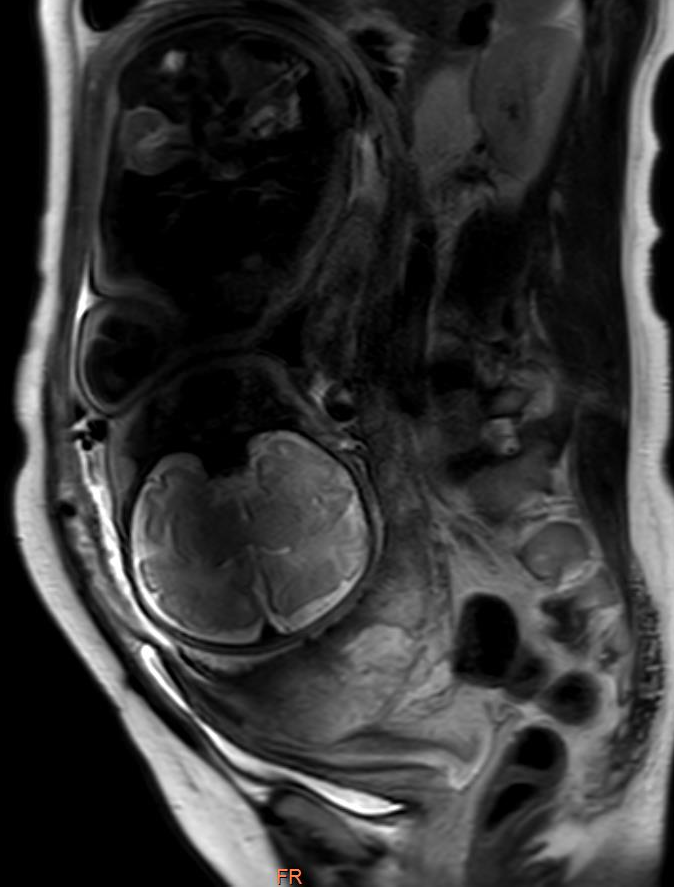

影像显示:前置胎盘并胎盘植入

了解情况后,影像科应用飞利浦3.0T超导磁共振迅速为患者进行了检查,影像科技术人员操作熟练、检查细致规范,图像多方位采集,清晰显示患者病情,影像科医师阅片与检查同步进行,认真及时分析图像,发现郭女士为胎盘前置,完全覆盖宫颈管内口,胎盘与子宫剖宫产术后瘢痕分解不清,胎盘下见粗大血管影及少量出血信号,存在胎盘植入。

前置胎盘并胎盘植入影像

前置胎盘并发胎盘植入是产科严重的并发症,常引起大出血,甚至休克,增加子宫切除率,严重危及产妇及胎儿安全。据悉,前置胎盘患者并发胎盘植入的发生率高达50%。术前准确诊断可指导手术方案的制定,因此,及时准确的诊断对孕产妇至关重要。目前,前置胎盘并胎盘植入的影像诊断主要依据经腹超声探查,但该方法易受孕妇及胎盘位置的影响,诊断准确率较不固定。MRI快速扫描技术发展迅速,已逐步应用于胎盘疾病的诊断。